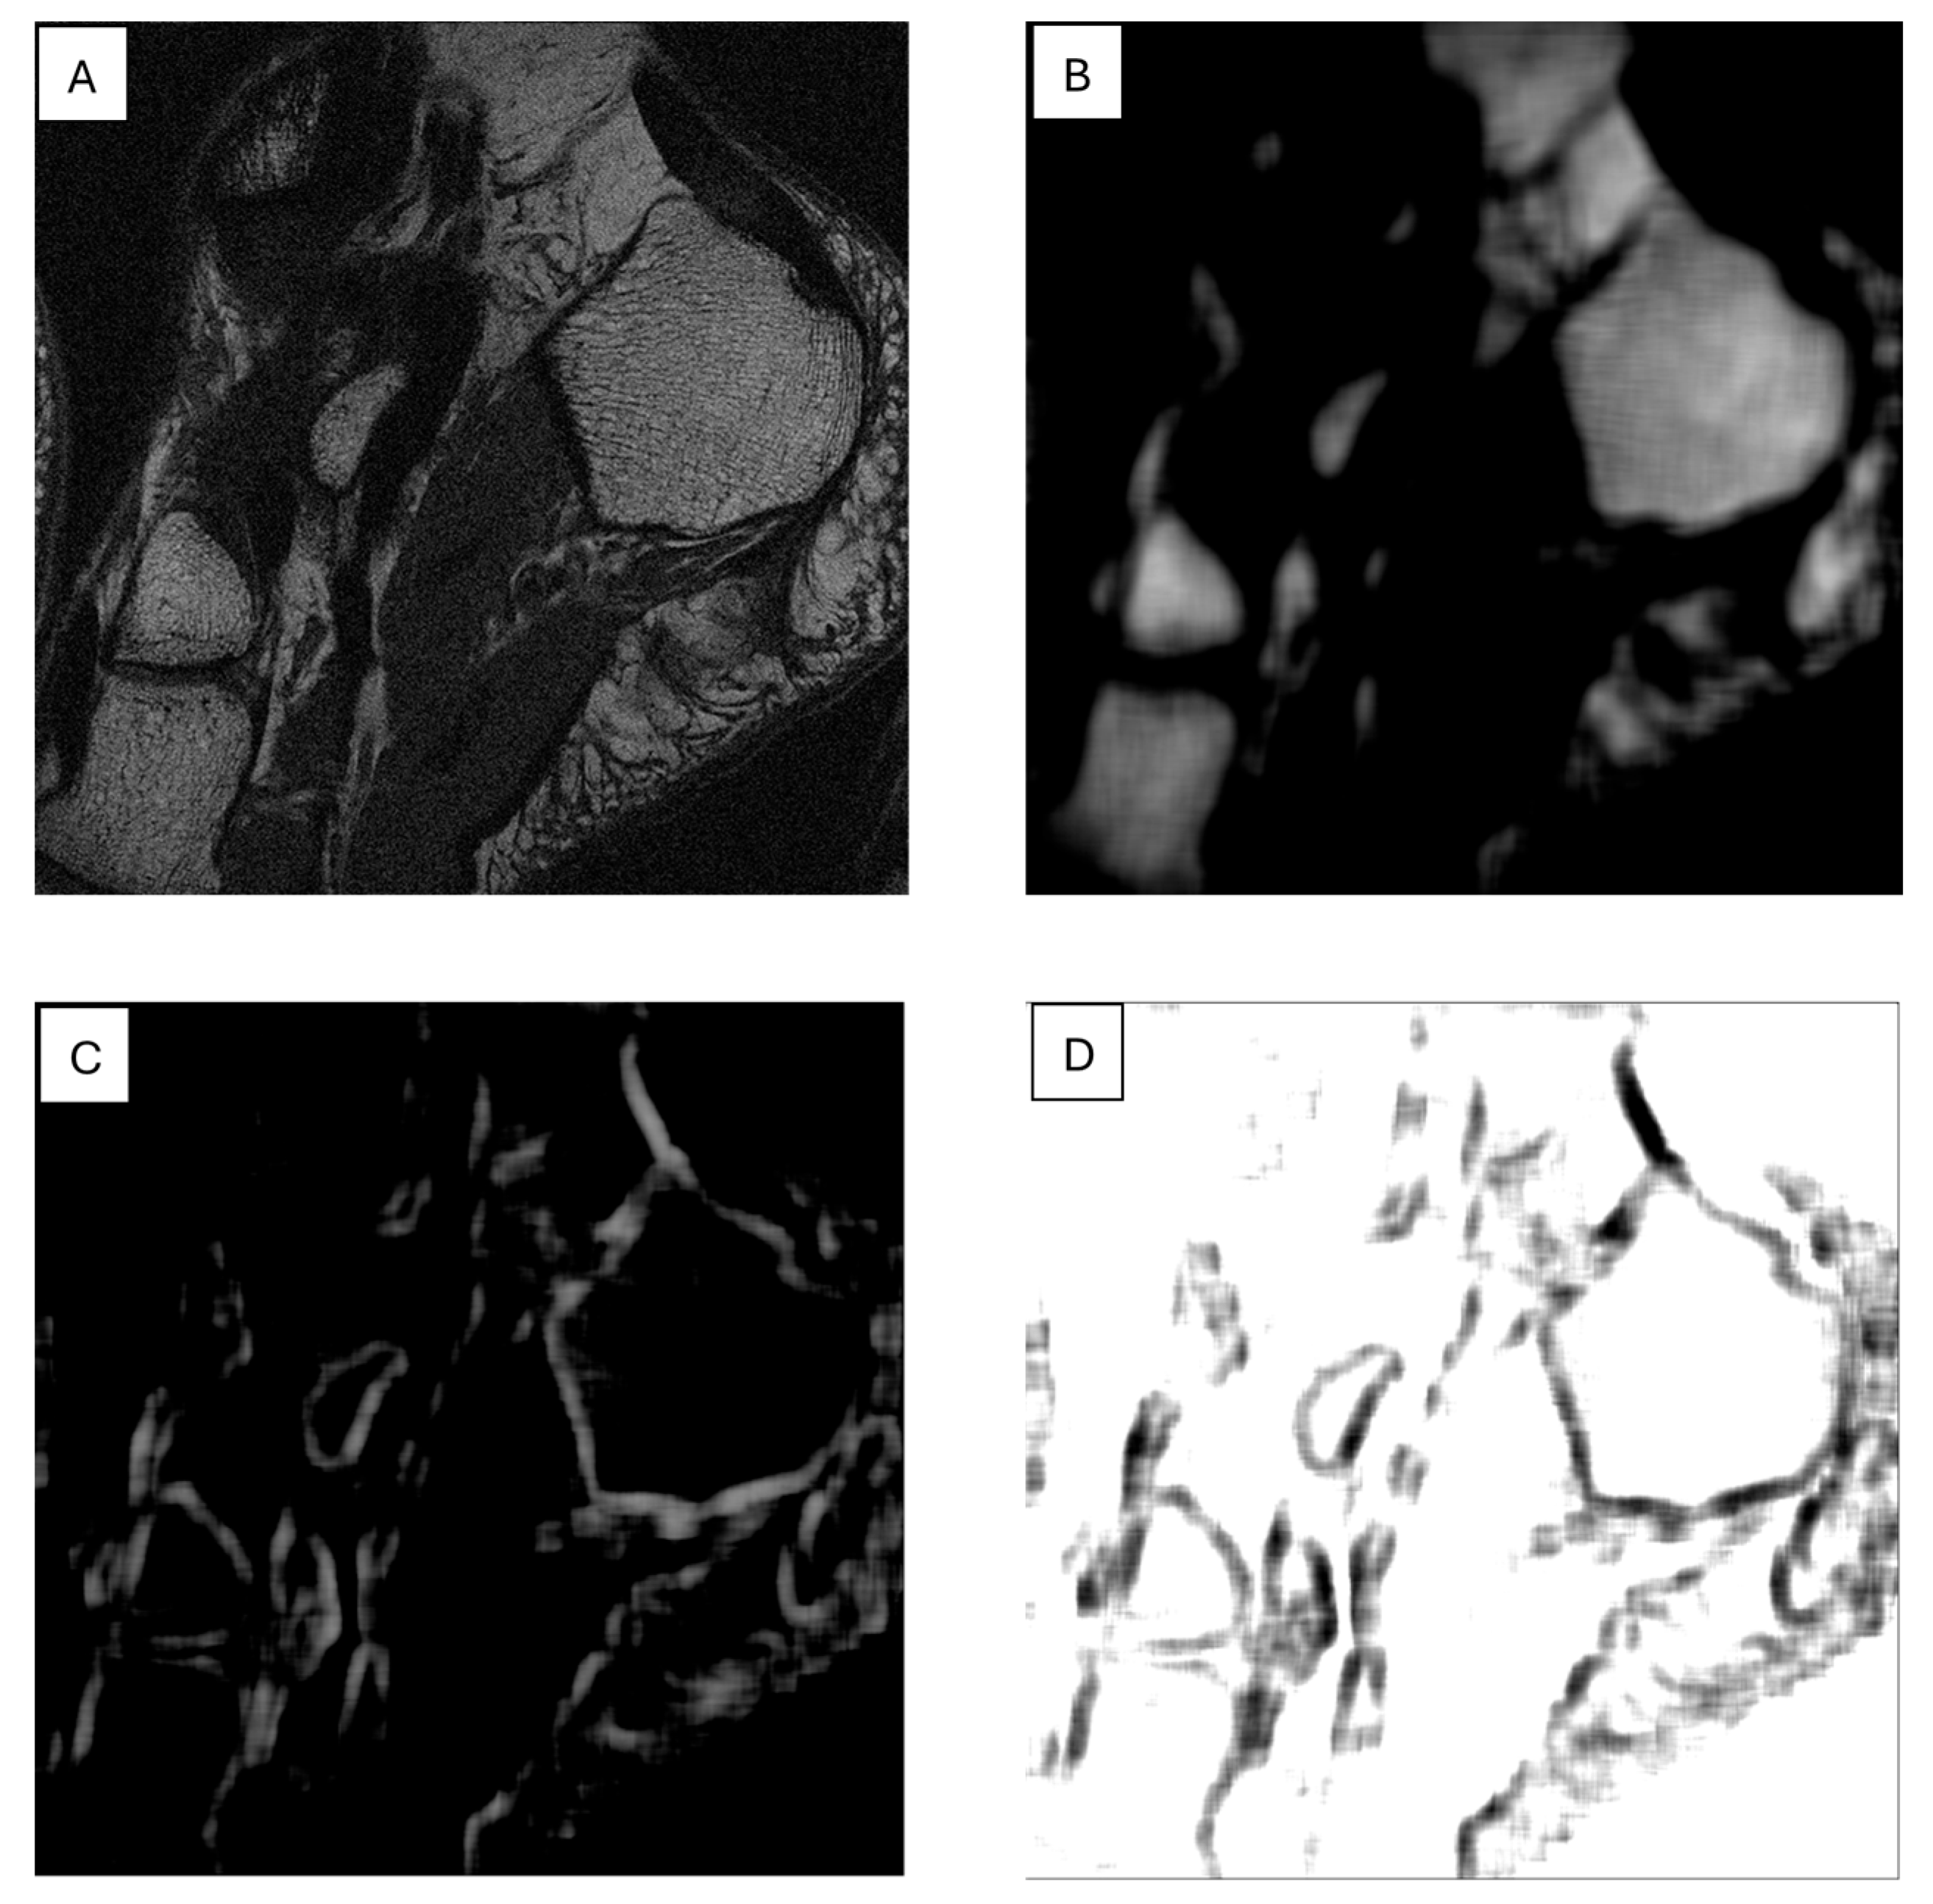

7. The Role of Textural Analysis in Image Preprocessing